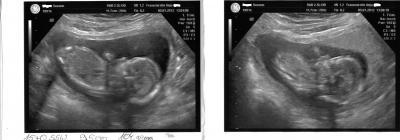

Hallo Ihr lieben, nach dem ich mit Termin heut 3 STUNDEN !!!warten musste habe ich noch erfahren das Sie keinen Ultraschall macht ok dachte ich mir dann Bezahle ich halt hauptsache ich seh mein Baby . Gesagt getan meinem Baby geht es super es hat Geschlafen aber sowas von Süss das glaub ihr garnicht. Er ist 9,5 cm "groß" und 104 gramm "schwer". Sie hat auch noch mal gesagt das er (warscheinlich) ein Junge wird. ich bin heute 15+0 ssw laut untersuchung 15+2 ssw. Ach Mädels ich freu mich so das mit meinem Baby alles ok ist aber ein wehmutstropfen gab es noch ich habe 1,6 kg zugenommen ich habe gefragt ob das ok ist und sie sagte ja beim 2 kind nimmt man schneller zu na toll das macht mut . so jetzt möchte ich euch nicht weiter stören. ich hänge euch noch die Bilder von heute an lg und einen schönen abend

Bild zu Bericht vom Frauenarzt + Fotos - Forum für Juli - Mamis

Erstmal muss ich sagen, dass dein Kleiner echt knuffig ist... schöne und recht eindeutige Bilderchen und wow er ist schon fast 10cm groß... ist das die Gesamtlänge oder SSL? Und mir ist aufgefallen, dass der kleine Mann ja jetzt schon schwer ist wie ne Tafel Schoki echt toll. Wieviel musstest du den für den US bezahlen?... aber gut, dass du es gemacht hast, nun biste beruhigt und weißt sogar was es wird... hätt ich auch gemacht... LG deine Keksi

schön, dassdein baby so toll gewachsen ist. es sieht wirklich nach einem jungen aus. schöne fotos.